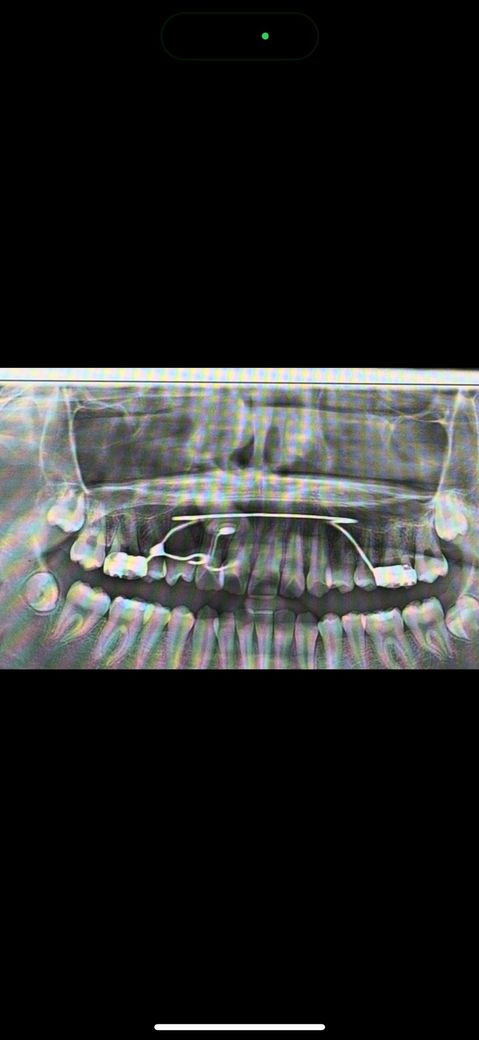

제가 현재 오른쪽 송곳니가 매복되어 있어서 입천장에 버튼을 달고 견인 중인데요. 이제 견인을 시작한지 6~7개월정도가 지났고 사진은 7전에 찍은 사진입니다. 치과에서 매복치를 일자로 세운후 잇몸을 잘라서 꺼낸다고 했어요. 앞으로 매복치가 일자가 되는 데 얼마나 더 걸릴까요? 나이는 현재 중학교 3학년입니다.

• 1번 째 사진

보통 3-6개월은 예상해야 합니다. 중3이니 조금 더 빨리 방향 전환이 가능한 경우도 있습니다.

지금 사진만으로는 정확히 알 수 없으나 방향에 따라 그리고 매복 정도에 따라 다릅니다. 얕게 매복되어 있고 치근과 겹쳐져 있지 않다면 3~6개월 걸리겠지만 깊게 매복되어 있고 치근과 겹쳐져 있다면 12~18개월 혹은 그 이상도 걸릴 수 있습니다. 지금 사진으로는 정확한 판단이 어려우며 dental-ct가 있어야 정확한 판단이 가능합니다.

사람마다 다릅니다. 보통 매복치아 견인에 걸리는 시간은 보통 6~12개월 정도입니다. 매복정도, 치아 치근 발육 정도에 따라 다릅니다.